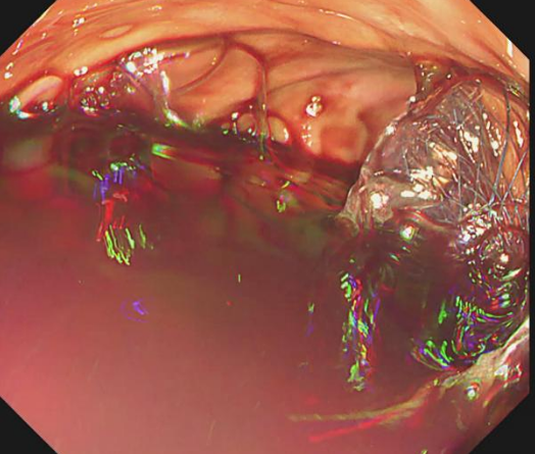

左图术后4天,可见大量坏死物堵住支架,“双支架”发挥重要作用;右图术后4周,支架、营养管位置良好,包裹性坏死腔内新鲜肉芽组织

术后四周,孙家琛为李阿姨取出LAMS支架,并夹闭了创面。经过治疗,李阿姨顺利出院,出院前复查

左图取出支架后经胃观察包裹性坏死腔,为新鲜肉芽组织;右图胃镜观察取出支架后的创面